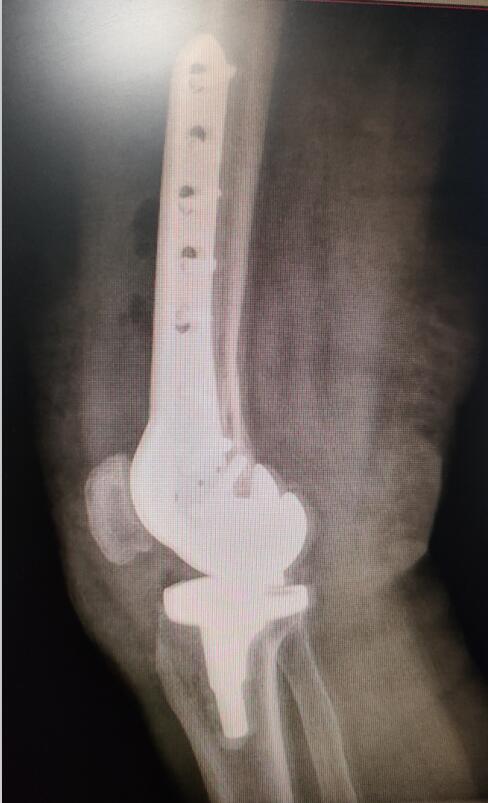

手術(shù)后照片

12月7日,在醫(yī)護團隊的默契合作下,歷時1個多小時,吳阿姨的手術(shù)順利完成。經(jīng)過兩周的后續(xù)治療,吳阿姨已經(jīng)可以站起來,借助拐杖行走?!搬t(yī)生們這次又讓我站起來了?!眳前⒁涕_心地說。